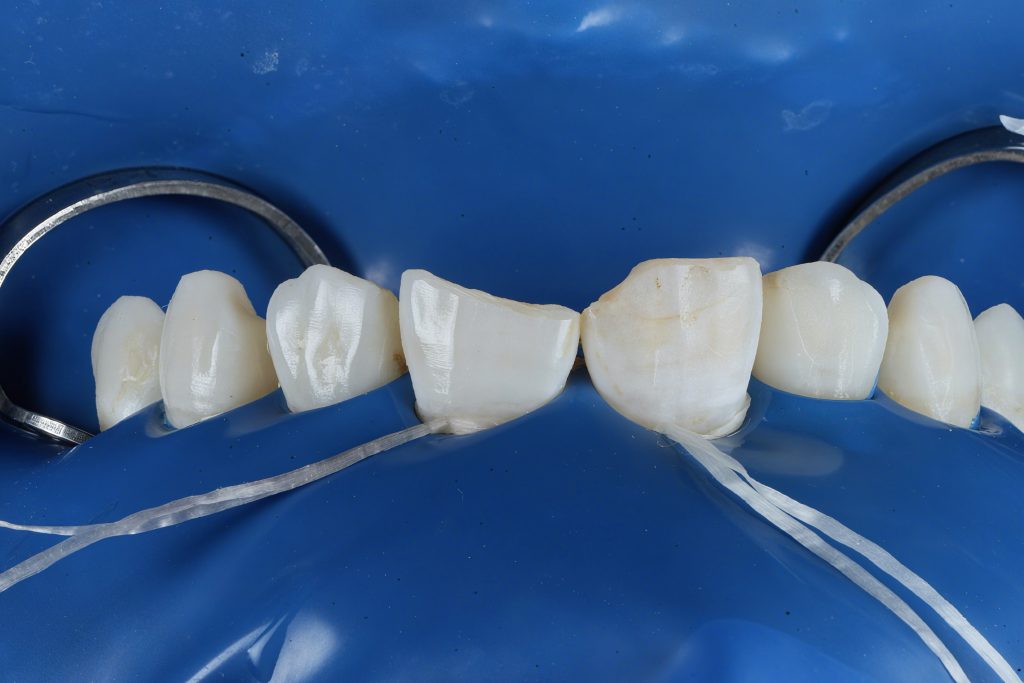

STEP 1 – Rubber Dam Isolation

Full arch rubber dam isolation was placed to secure a sterile adhesive environment and retract soft tissue. (Fig.1)